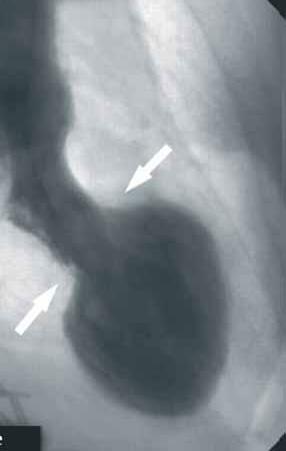

Angiogramma in diastole (sinistra) e sistole (destra) in proiezione obliqua anteriore destra che dimostra l’anomalia del movimento della parete caratteristica della cardiomiopatia da stress. Alla fine della sistole, la camera ventricolare sinistra adotta una configurazione distintiva a “collo corto con pallone tondo” in cui la porzione distale (apicale) è acinetica/ipocinetica mentre, al contrario, il restante segmento prossimale (basale) è ipercontrattile (l’area di transizione affilata è mostrata dalle frecce).

Nella foto: Angiografia coronarica di paziente 82enne affetto da Sars-Covid 19. L’immagine ha mostrato arterie coronarie prive di lesioni ed è stata eseguita la ventricolografia cardiaca. Ciò ha mostrato una frazione di eiezione ventricolare sinistra molto ridotta con ampia acinesia apicale. Il risultato della PCR è stato positivo, indicando la sindrome Takotsubo correlata all’infezione virale. Rivista spagnola di Cardiologia DOI: